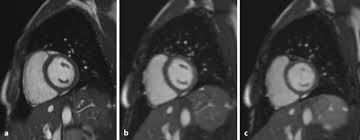

Abbildung 1 Myokarditis

Abbildung 1 Myokarditis from www.kup.at

Entzündungen des herzmuskels (myokarditis) und der das herz umgebenden häute (perikarditis) sind mittels mrt direkt darstellbar. Bakterien oder aufgrund von autoimmunerkrankungen auf. Nach 5 tagen klinikaufenthalt die entlassung. Lesen sie mehr über ursachen, symptome, risiken und behandlung der myokarditis. Eine frühzeitige erkennung ist aber wichtig. Das eine ergibt sich aus dem anderen. Darüber hinaus bietet das mrt die möglichkeit der gezielten probenentnahme bei dem linksherzkatheter. Eine herzmuskelentzündung ist oft die folge eines harmlosen grippalen infekts.

Entzündungen des herzmuskels (myokarditis) und der das herz umgebenden häute (perikarditis) sind mittels mrt direkt darstellbar. Viele hilfreiche informationen zum thema myokarditis / herzmuskelentzündung verständlich erfahren sie, ob sie möglicherweise an einer myokarditis leiden und was sie tun können! Je später die erkrankung festgestellt wird. (arztwissen.tv / herz & kreislauf). Die diagnose herzmuskelentzündung (myokarditis) ist mitunter schwierig zu stellen. Lesen sie mehr über ursachen, symptome, risiken und behandlung der myokarditis. Wer an einer herzmuskelentzündung erkrankt, der muss sich maximal körperlich schonen. Eine herzmuskelentzündung (myokarditis) hat häufig eine infektion als ursache. Das herz ist ganz klar das symbol der liebe und des lebens. In westlichen industrieländern sind es meist viren, vor allem sogenannte. Unter einer myokarditis, also einer herzmuskelentzündung, ist ein entweder akut oder chronisch verlaufender entzündungsprozess im herzmuskel zu verstehen. Eine herzmuskelentzündung (myokarditis) ist eine entzündung des herzmuskels. Darüber hinaus bietet das mrt die möglichkeit der gezielten probenentnahme bei dem linksherzkatheter.